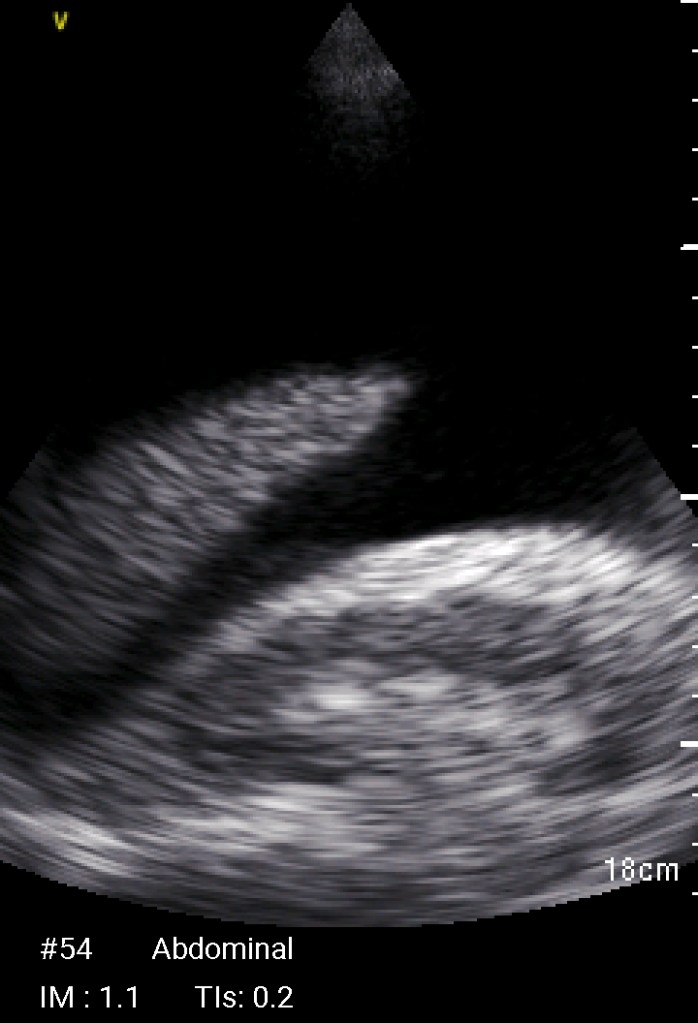

Echographie Sous-clavièreJugulaireFémorale JUGULAIRE G FEMORALE Dt MorissonKohlerDouglas Sous-clavièrePleural J’aime chargement…